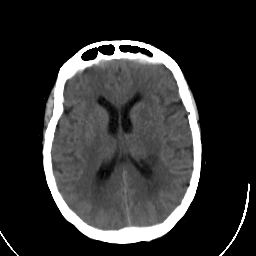

Stroke CT #3 -- Slice #14

[Home][Help][Clinical] Slice 14